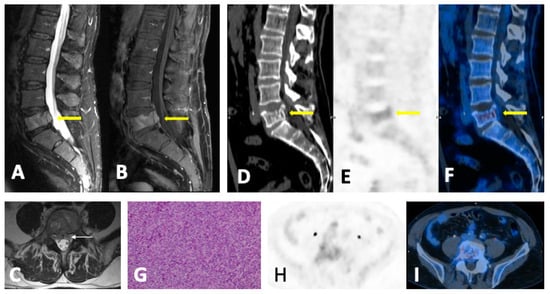

- Diffuse pattern: Diffuse disease can be suspected from a diffuse decreased signal on T1WI (either iso- or hypointense to intervertebral discs and muscle) and a diffuse increased signal throughout the marrow on T2FSWI, STIR, or high b-value DWI. Marrow ADC values above 600–700 μm2/s in a nontreated and newly diagnosed patient with MM could be used to increase confidence for the diagnosis of diffuse marrow involvement [33] (Figure 7). Due to potential false-positive findings, diffuse disease in imaging must be supported by bone marrow trephine biopsy [26].